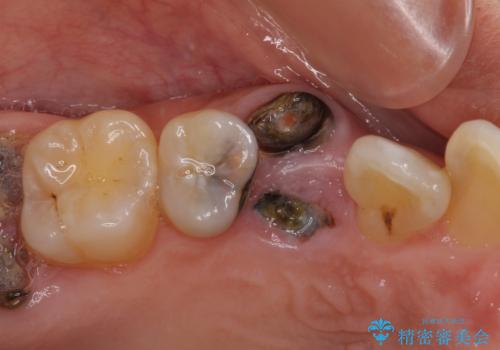

- 前歯などに、むし歯でボロボロになった歯があるとのことで来院された患者様です。

むし歯により歯冠が崩壊してから長いこと経過しているとのことで、歯を失ったことによる他の歯への影響はあまりないと判断されたため、審美領域である上顎前歯部のみにインプラント補綴治療を行うこととしました。

2本の歯が前後に重なった状態でむし歯となっていたので、抜歯後に歯肉や骨の状態が落ち着くのを待ち、インプラントを埋入することとしました。